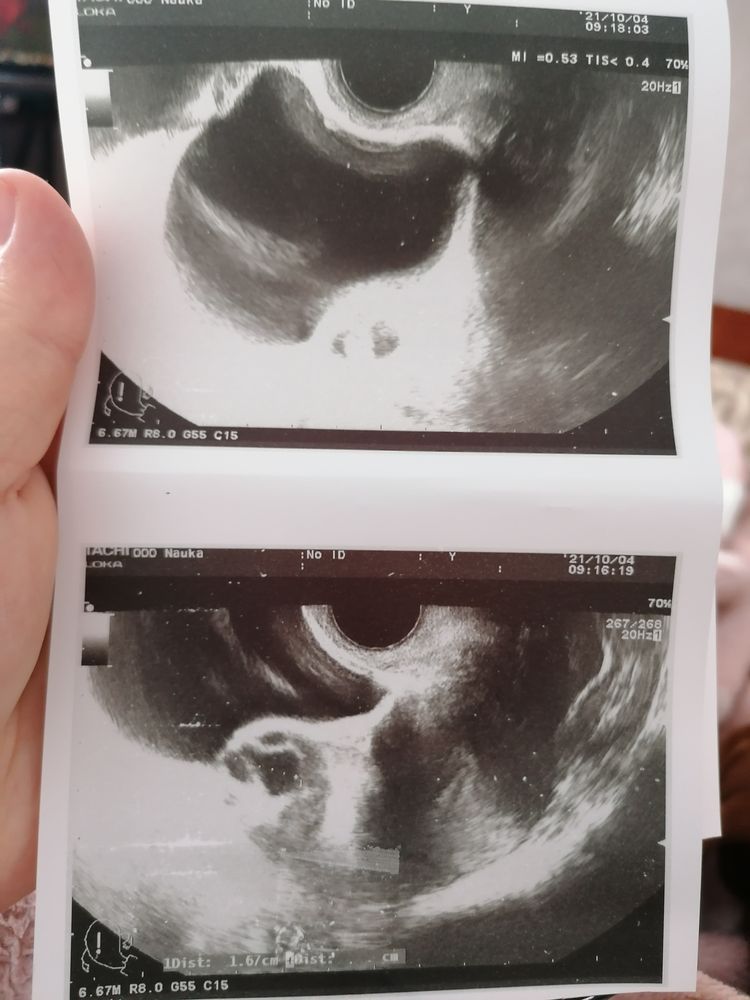

Christina, эндометрий им наращиваю) свой маленький обычно, а тут за 3 дня с 7 до 12 аж подрос)

Буду мамой , ходила на 13 дц, фолликул был 19 мм, а сегодня 17 дц, лопнул на 14-16 дц. Точно не знаю овуляцию , по тестам не отслеживала и я её особо не чувствую)